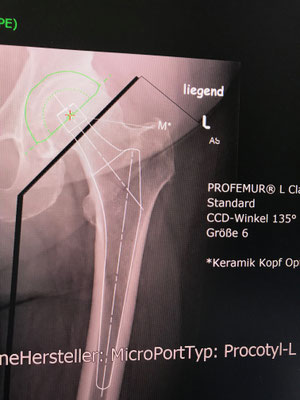

An der Hüfte setzen wir auf langjährig bewährte Implantate, die nachweislich über Jahrzehnte gute Ergebnisse liefern. Wir versuchen, wenn möglich, größere Standardkugeln einzusetzen um eine möglichst gute Beweglichkeit zu erreichen. Leider hatten bisherige "moderne" neue Hüftgelenke immer wieder Probleme, sodaß diese relativ schnell vom Markt wieder verschwanden ( z. B. Roboterhüfte, Computer designed Prothese, Oberflächenersatz).

Jede Hüftprothese wird zuvor, wie in einem Ingenieurbüro am Computer geplant (siehe Bild im Link Praxis) und ausgemessen, um diese Werte möglichst in der Operation umzusetzten. Ziel ist es, ihr eigenes Gelenk so zu ersetzen, daß ihr Muskelzug und Kraftübertragung erhalten bleibt und die Prothese optimal eingepaßt wird.